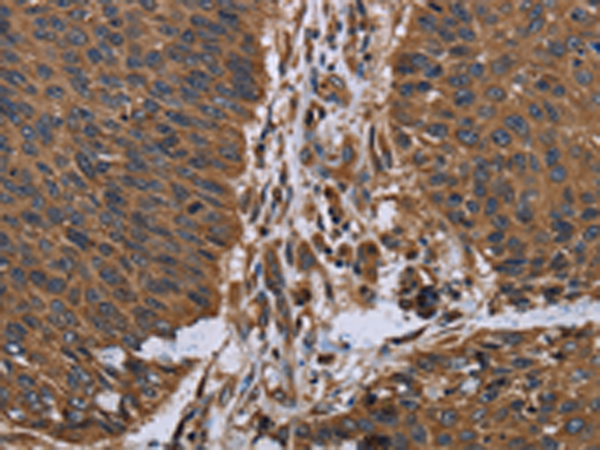

分类: 科研抗体货号: P01512别名: GRCB; LEPREL2; HSU47926应用: WB,IHC反应种属: Human, Mouse